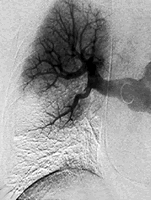

美国Lehigh Valley医院肿瘤中心Martino医师等的一项研究表明,即便使用间断充气加压治疗预防血栓栓塞,接受大型经腹手术的妇科肿瘤患者发生肺栓塞的几率仍会显著增高。

研究纳入了1373例在2001年6月至2003年6月因妇科肿瘤接受手术治疗的患者,她们均接受了间断充气加压治疗并在术后早期下床活动,以预防静脉血栓形成。Martino医师等将患者按术式(大型、小型经腹手术或非经腹手术)、诊断(恶性或非恶性)和癌症亚型进行了分组,并用 2检验和逻辑回归模型比较了各组的数据。

结果表明,有839例参试患者接受了大型经腹手术,其中有507例被确诊为恶性肿瘤,332例为良性病变。有534例患者接受了小型经腹手术或非经腹手术。接受大型经腹手术的恶性肿瘤患者肺栓塞的发生率为4.1%(51/507例),而接受大型经腹手术的良性病变患者肺栓塞发生率仅为0.3%(1/332例)(P<0.001,OR=13.8)。接受小型经腹手术或非经腹手术患者的肺栓塞发生率为0.4%(2/536例)。被确诊为癌症和患者年龄>60岁均为发生肺栓塞的危险因素(P=0.009,OR=0.31)。发生和未发生肺栓塞患者的一年生存率分别为48.0%± 12%和77.0%±2%。[Obstet Gynecol 2006, 107(3)∶ 666]

研究提示:即便使用间断充气加压治疗预防血栓栓塞,接受大型经腹手术的癌症患者肺栓塞的发生率仍较因良性病变接受手术的患者高14倍。仍需进行随机研究,确定是否需要对肺栓塞高危患者采取额外的预防性措施。, http://www.100md.com